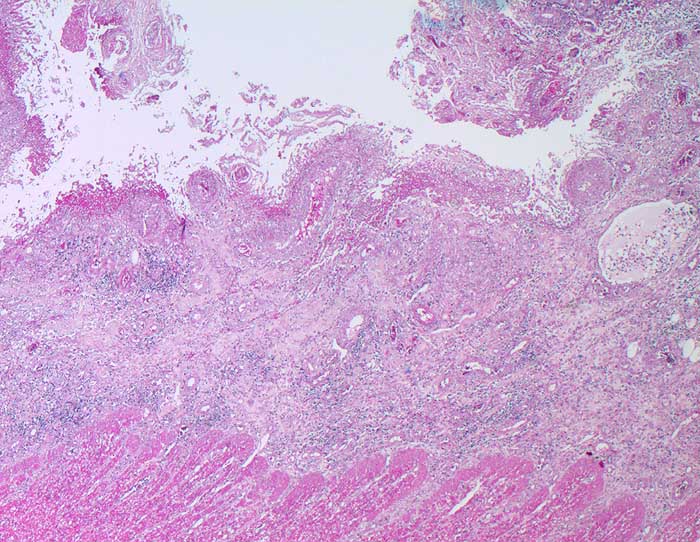

AP/ Amöbenkolitis

Amöbenkolitis

Entzündung infektiös

Darm, Anus

Kolon

Makroskopie